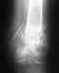

Re: деформирующий артроз таранно-пяточного сутстава